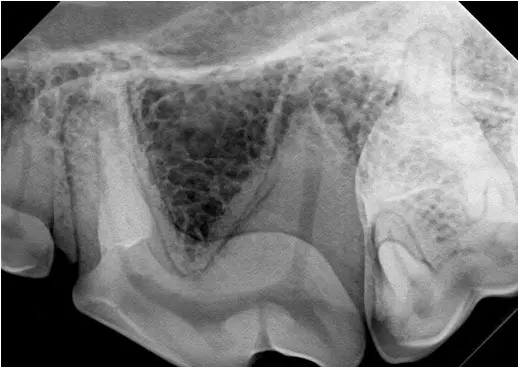

Left side of the same patient, shown for comparison. These teeth were normal on oral exam.

While 108 has a small uncomplicated crown fracture, the tooth appears vital at this time. The root canals of 108 and 208 are both of similar size and the periodontal ligament space (pdl) is visible around the distal root of 108. The uncomplicated crown fracture of 108 should be treated with bonded sealants at this time, with follow-up radiographs of that tooth being taken in 6-12 months to ensure that the tooth remains vital. For more information on the potential ramifications of small cusp tip fractures, click this link to see a past newsletter on this topic: fractured teeth